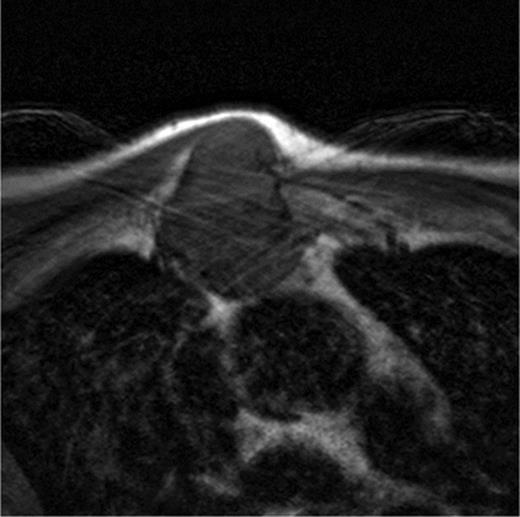

A 60-year-old male patient presented himself to the outpatient clinic of our department with a progressive sternal mass. An MRI scan indicated a tumour involving the manubrium extending to the first and second ribs and involving the right clavicle and sternoclavicular joint (Figs 1 and 2). Based on radiological evaluation, a core biopsy was obtained and a low-grade chondrosarcoma was characterized. Radiological evaluation indicated primary tumour resection to be the treatment of choice. Radical excision of the tumour was performed and resulted in resection of the manubrium, as well as the medial third of the right clavicle and the right first and second ribs. Steel wires through the sternum and left sternoclavicular joint spanned the 6.5 cm sternal defect (Figs 3 and 4) and a polypropylene mesh filled with methyl methacrylate composite (Surgical Simplex®), Howmedica Osteonics, Limerick, Ireland, was placed, yielding a stable reconstruction of the sternal defect (Figs 5–8). The sternocleidomatoideus muscle was re-inserted to the polypropylene mesh. Pathological examination showed complete excision of the tumour. The patient recovered uneventfully and was discharged 7 days post-operatively. At seven year follow-up, the patient displayed excellent functional and aesthetic results. Optimal function of his shoulders allowed a complete return to work and other activities without disabilities.

The axillar slides of the MRI of the patient showing the ingrowth of the tumour in the thoracic cavity in relation to the intrathoracic organs.